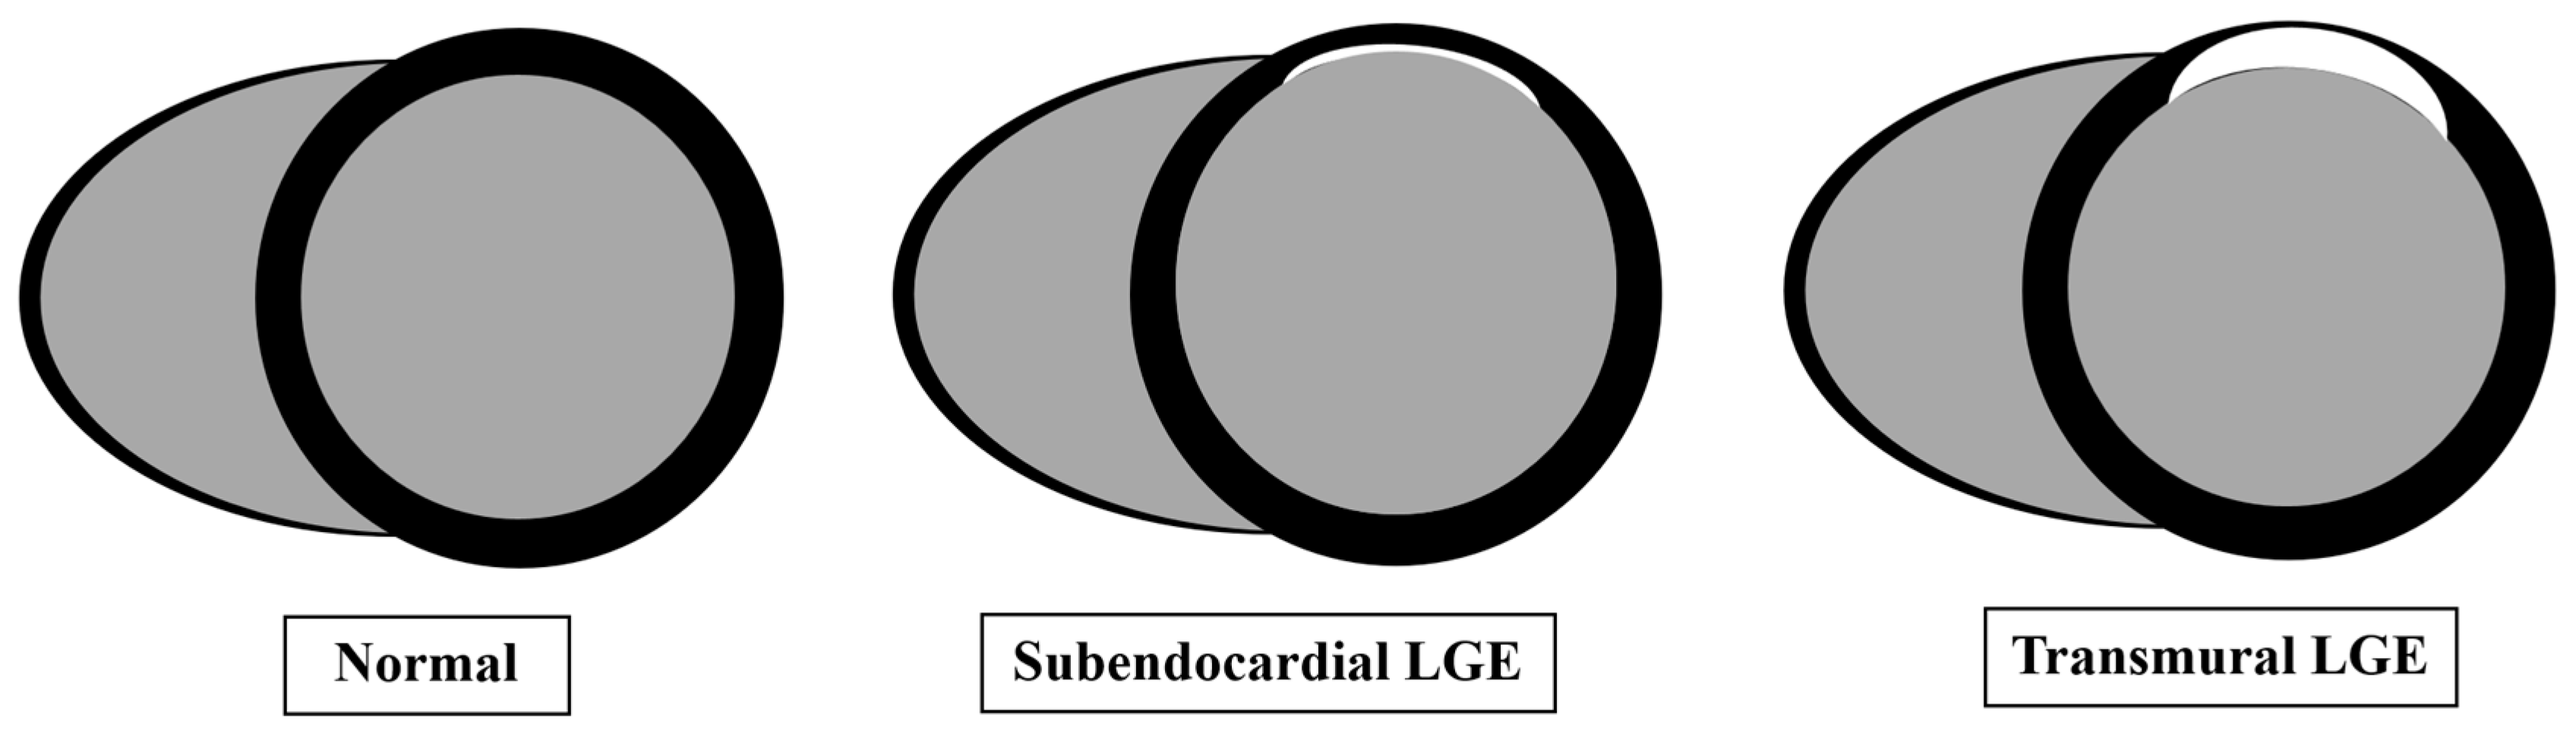

| Late gadolinium enhancement (LGE) | LGE imaging: magnitude and phase sensitive inversion recovery | Short-axis stack Long axis-single slice: 2 chamber, 3 chamber, 4 chamber view | Detection of infarction or fibrosis |